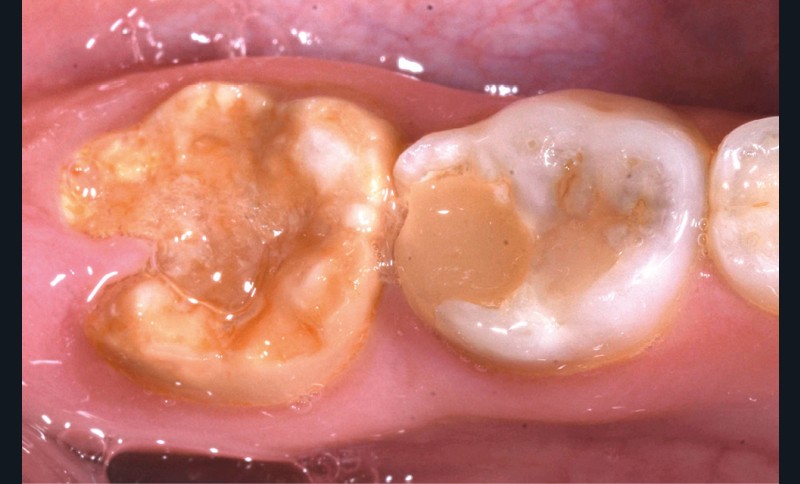

Une patiente de 10 ans se présente en consultation. Aucun antécédent médical ou chirurgical n’est constaté. À l’examen clinique, nous observons une forme sévère de MIH sur 36 et 46 avec des fractures post-éruptives [1] (fig. 1a et b). En raison de cette pathologie, la patiente se plaint de sensibilités spontanées sur ces dents, ayant un impact sur sa qualité de vie, et une maîtrise difficile de l’hygiène bucco-dentaire. Les secteurs antérieurs maxillaires et mandibulaires présentent aussi des opacités délimitées entraînant une gêne esthétique conséquente pour la patiente.